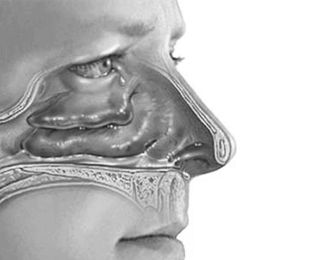

Методи діагностики алергічного риніту МКБ включають огляд пацієнта, складання переліку симптомів, визначення ступеня їх тяжкості, спостереження клінічної картини, призначення шкірних проб, аналізу крові, мазка з носової порожнини, а також інструментальний метод - риноскопию.

Визначити симптоматику хвороби самостійно допоможуть різні фото алергічного риніту в інтернеті, проте це можна розцінювати тільки як попередній непрофесійний діагноз.